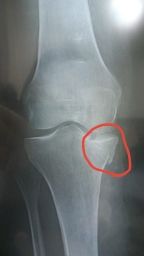

Perso les révisions ça fait loin pour l'orthopédie et c'est pas le truc où j'ai été le meilleur...puis son cliché est pas ouf niveau qualité même si on voit la fracture

Après j'ai des livres de traumato et d'imagerie mais y'a pas tellement de clichés dessus et généralement ils sont quand même de meilleur qualité avec aucun reflet chelou et un bon contraste.